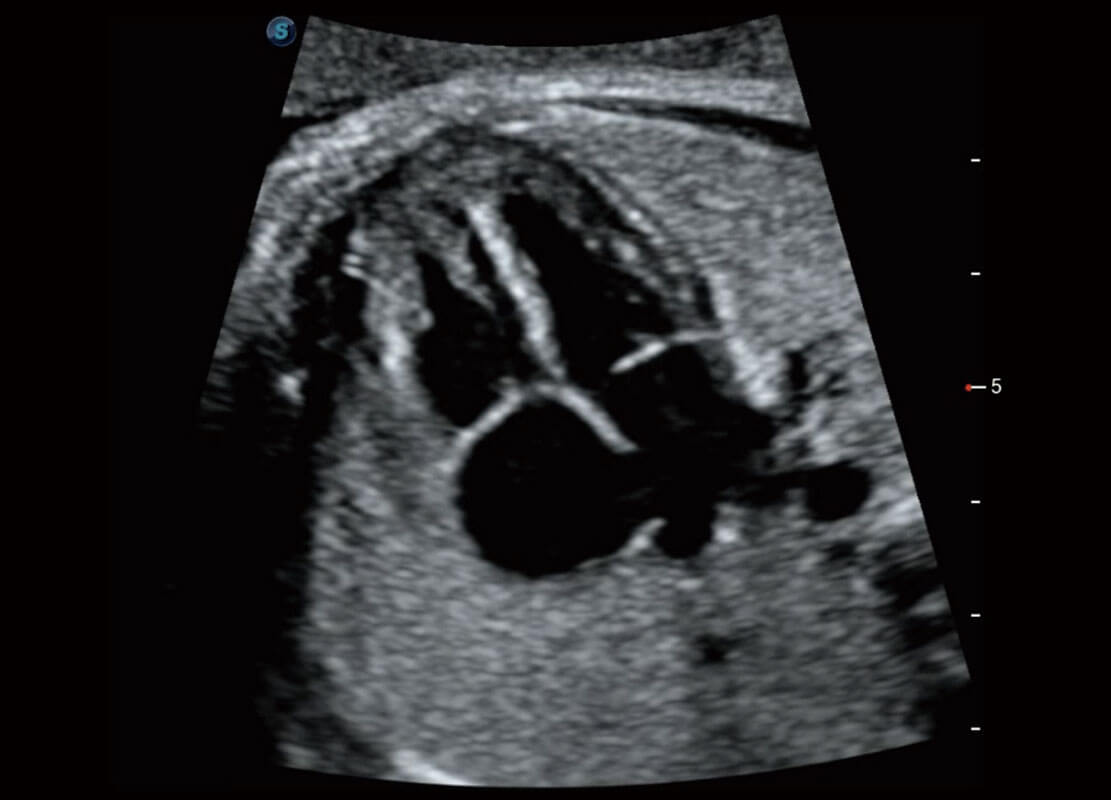

P60搭载一系列胎儿心脏成像技术,实现精细的胎儿心脏评估。

• 四腔切面

• 四腔心血流

• 右室双出口

• 胎心容积成像